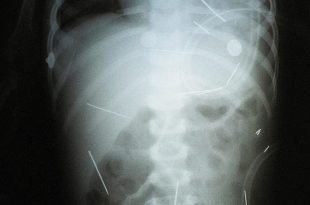

Saiba Mais »O Índice da Maldade e o Caso do Padrasto que feriu uma criança com 50 Agulhas num Ritual de Magia Negra

O Índice de Maldade é uma escala com 22 níveis, criada pelo Dr. Michael Stone …